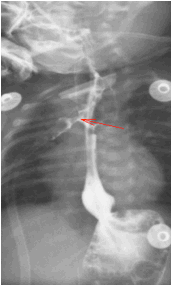

图 4 吻合口漏消失,出现吻合口狭窄

10-19 造影检查: 上消化道造影 (数字化摄影):食道闭锁术后改变,吻合口狭窄。食管裂孔疝;肺炎;近日患儿出现口水增多,考虑和食管狭窄有关,向家长告知病情,建议食管扩张,家长同意,故 2021.10.22 日在全麻下行经口球囊食管扩张术

入院诊断:入院后完善术前检查,给予箱内吸氧(3L/min),头孢他啶抗感染,维生素 K1 预防维生素 K 缺乏性出血,禁饮食、胃肠减压、补液等对症支持治疗。监测血压、血糖、心电、血氧。确诊食管闭锁。于 2021 年 8 月 19 日行经胸膜外食管吻合术,术后出现吻合口漏,感染指标上升。2021.09.05 根据引流液培养缓症链球菌,药敏结果选用头孢哌酮舒巴坦及万福霉素抗感染治疗,感染指标有所下降,但一直未正常,反复出现喂养不耐受,贫血等症状。先后多次因贫血输红悬液治疗。09.14 停用万古霉素抗感染。2021.09.24,取痰培养,2021.09.25 经验升级抗菌素为美罗培南抗感染。09.26 日行 mNGS 检测。09.27mNGS 结果回报提示为粘质沙雷氏菌,大肠埃希菌,缓症链球菌,产气克雷伯氏菌。同时痰培养结果回报。痰培养结果提示未大肠埃希菌但是几乎全部耐药,仅替加环素敏感。同时提示还有 CMV 感染。考虑多重感染可能性大,继续应用对粘质沙雷氏菌,大肠埃希菌,缓症链球菌,产气克雷伯氏菌等病原均有作用的美罗培南抗感染,同时停用对耳肾毒性较大的万古霉素抗感染。患儿精神状况好转,感染指标逐渐下降至正常,喂养耐受,肠内营养增加,贫血改善。2021.10.09 血常规及 c 反应蛋白正常,感染控制。2021.10.19 复查造影提示吻合口漏愈合(图 4)。10 月 22 日因食管狭窄再次行食管狭窄扩张治疗,术后恢复顺利,10.28 达到临床治愈出院。